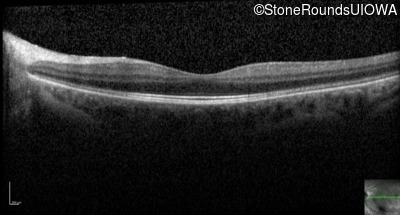

Optical Coherence Tomography - Left - 20/25 -1 sc

Exemplar / OCT Stack

OCT Stack